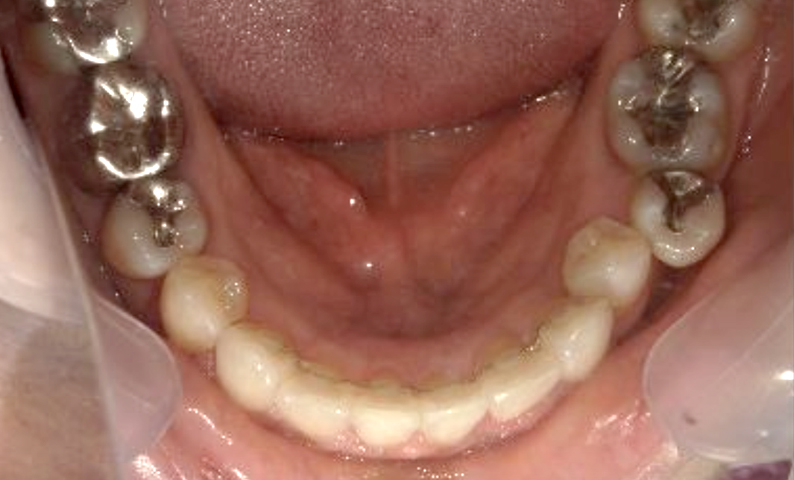

症例_003 下顎だけの部分矯正

治療期間:10ヶ月金額:24万円+税女性前歯のガタガタ下の前歯だけ上顎は補綴治療中

| Before | After |